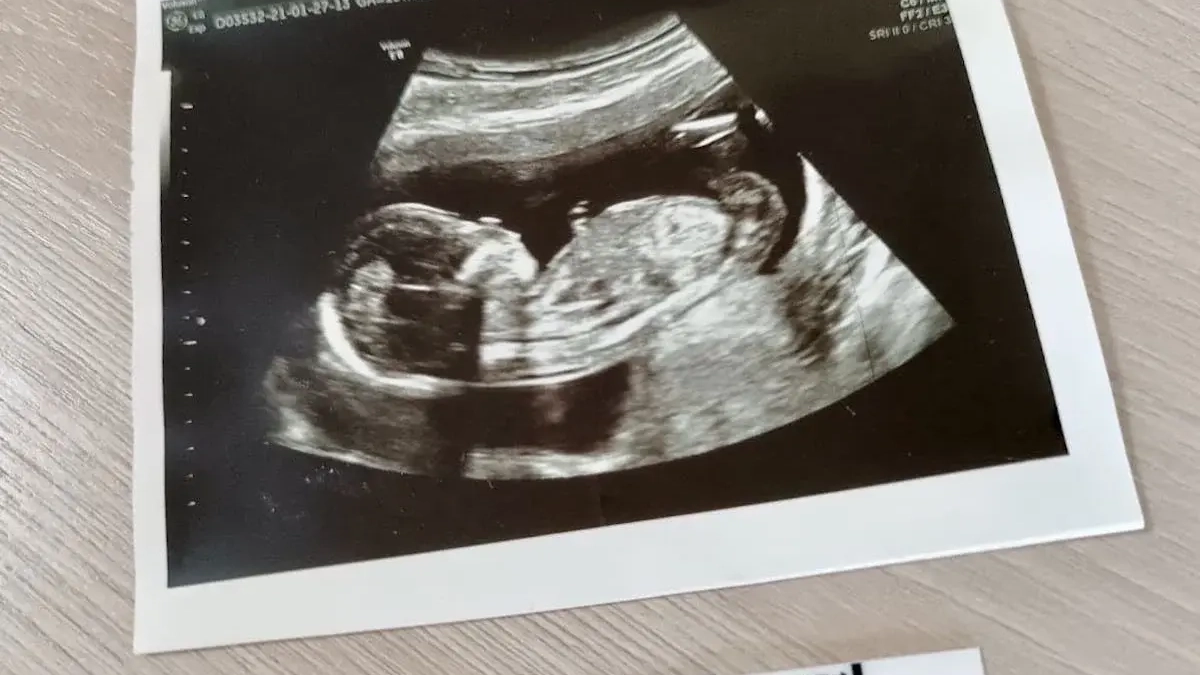

В Башкирии внедряют современные подходы к маршрутизации беременных, об этом сообщает "UfacityNews.ru".

В проект вошли 37 приложений, регламентирующих диспансерный учет, этапы скрининга на выявление хромосомных нарушений и пороков развития плода, а также действия врачей при преждевременных родах и других экстренных состояниях. Документ содержит протоколы взаимодействия с федеральными клиниками и алгоритмы ведения пациенток с эндокринными, сердечно-сосудистыми, онкологическими болезнями и инфекциями.